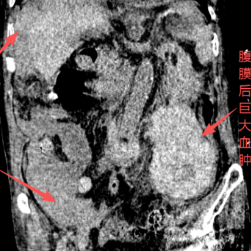

患者CT图片:可见腹膜后巨大血肿及腹腔大量积液等。

患者入院后,医院迅速完善各项辅助检查,确诊为腹膜后巨大血肿、腹腔大量积液、贫血,伴明显肠管水肿。医院胃肠外科第一时间启动应急救治流程,在专科主任曾之耀、主任医师桂双元的主持下,联合院内急诊ICU、介入科、血管外科、中心ICU、输血科等多学科团队,紧急开展联合会诊。

经综合评估,患者被判定为罕见的腹膜后血管畸形自发性破裂所致巨大血肿形成,且出血灶压迫肠管继发肠坏死,需立即实施外科手术干预。